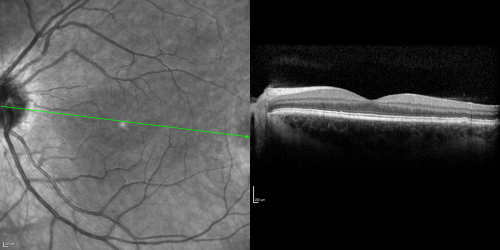

Basal Laminar Drusen - Cuticular Drusen - 19 Year Old with Lupus Nephritis

19-year-old.  She has a history of developing severe systemic lupus erythematosus in 2001.  She was in renal failure and had biopsy proven Class 2 lupus nephritis.  She is currently on Plaquenil 400 mg for six years, as well as Prednisolone orally, every other day. OD 20/20, OS 20/25.